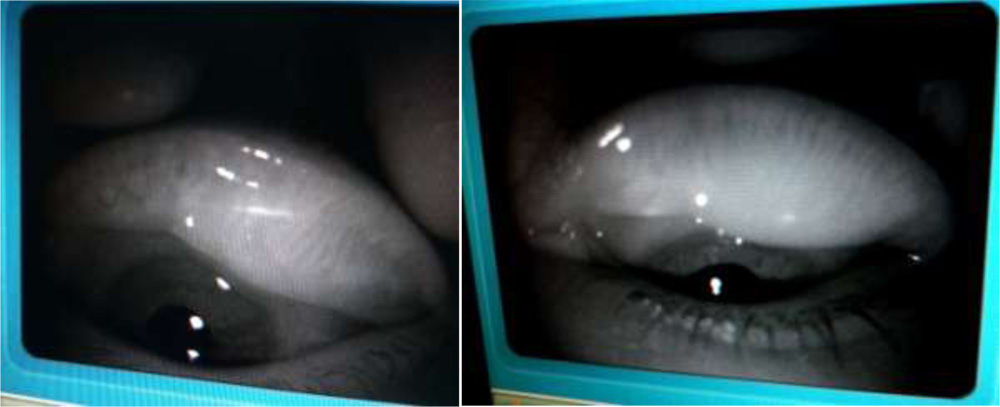

We tried to visualize the MGs by the infra red imaging using autorefractomer (Topcon RM8900), non contact tonometer (CT 80 Topcon), fundus camera (Zeiss), Zeiss  IOL master 500, specular miscroscope ( Topcon SP-3000p), ATLAS 9000 topographer and Visante AS-OCT which we have in our hospital. The images obtained were good enough to visualize the morphological features of MGs in these MGD eyes. We noted gland tortousity, shortening of the glands, broadening of the glands and gland drop-outs to various extent in many eyes. The images obtained by autorefractometer, IOL master, specular microscope, fundus camera, corneal topographer and Visante AS-OCT were better than those obtained by non-contact tonometer (NCT). The central shadowing of NCT while noting the MGs obscures the full visualization of MGs. The sample images obtained from these above mentioned instruments are as follows:

Autorefractometer:

IOL Master: